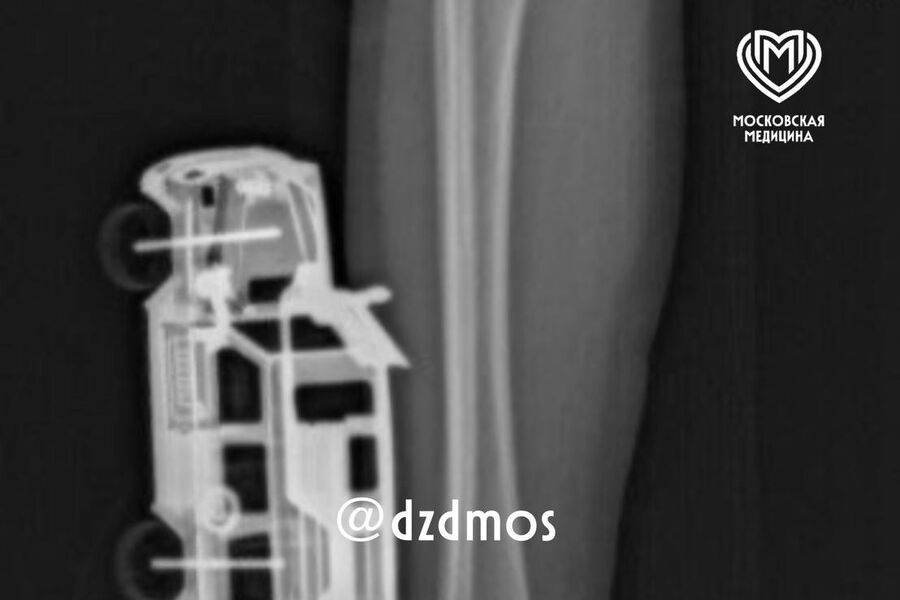

Столичные врачи спасли четырехлетнего мальчика с игрушечной машинкой в ноге

В Москве врачи спасли мальчика с игрушечной машинкой в ноге

В Москве четырехлетний мальчик упал на игрушечную машинку и оказался в больнице. Об этом сообщает Telegram-канал «Московская медицина».

По словам родителей, ребенок прыгнул с кровати у себя дома и неудачно упал на игрушку правой голенью. Машинка повредила мягкие ткани, ее части вошли глубоко и достигли подкожножировой клетчатки.

Пострадавшего мальчика доставили в больницу, где ему сделали рентген, чтобы исключить повреждение костей. После этого медики удалили игрушку и провели хирургическую обработку образовавшейся на ноге ребенка раны. Через сутки малолетнего пациента уже выписали домой.